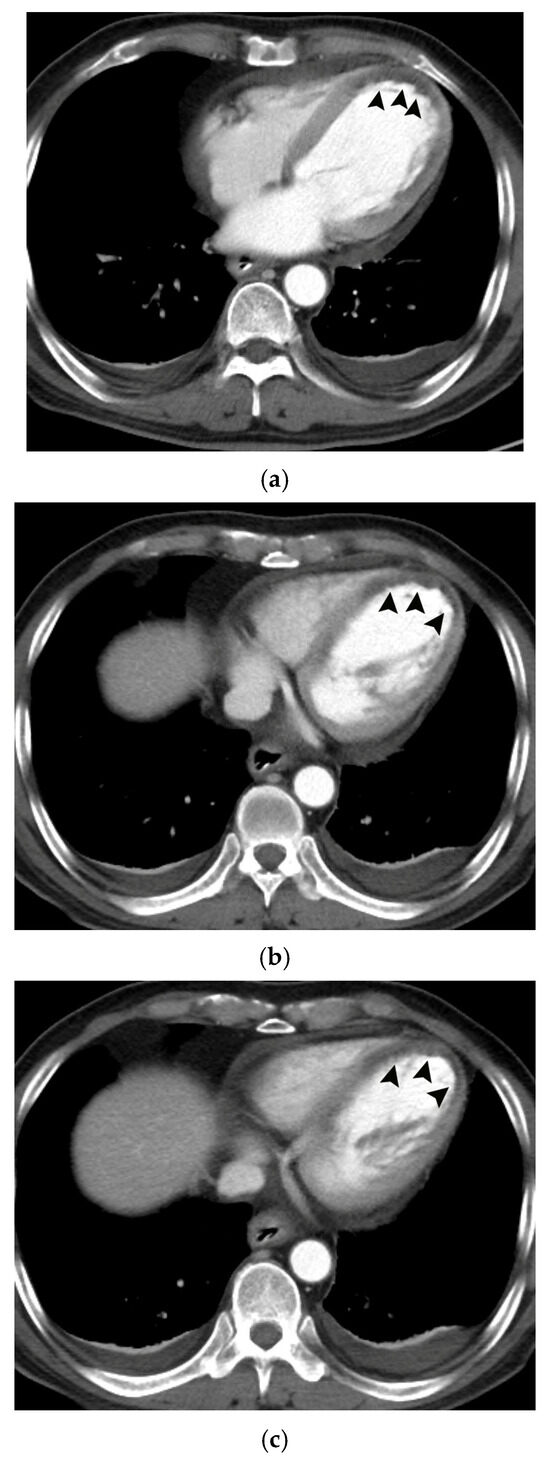

![Pathophysiology of migraine within the trigeminovascular system. (1) Mechanical dilation of the MMA increases Intercellular Adhesion Molecule 1 (ICAM-1) and Vascular Cell Adhesion Molecule 1 (VCAM-1) which support immune cell recruitment. It also activates perivascular trigeminal nociceptors, (2) leading to action potential propagation and calcium-dependent neuropeptide release. (3) Released mediators amplify migraine signaling through vascular and inflammatory pathways. Calcitonin-Gene Related Peptide (CGRP) and Neurokinin A mediate vasodilation, while Substance P causes mast cell activation. The substances released from mast cells have a variety of roles. Important for the pathophysiology presented, is that Tumor Necrosis Factor (TNF) alpha and Interleukin-6 (IL-6) increase CGRP release and C-C motif Chemokine Ligand 2 (CCL2) stimulates immune cell recruitment and neuronal CGRP reactivity, further amplifying the pathway [13]. Substance P may also be released by mast cells in certain disease states [13]. (4) These processes result in endothelial disruption with plasma extravasation (5) and edema-driven nociceptor sensitization [16]. Pharmacologic agents interrupt the cascade at discrete neurovascular nodes, with Lidocaine acting at sodium (Na+) channels and Calcium channel blockers acting at both nerve endings and plasma membrane of mast cells.](https://mdpi-res.com/cdn-cgi/image/w=470,h=317/https://mdpi-res.com/jvd/jvd-05-00009/article_deploy/html/images/jvd-05-00009-g001-550.jpg)